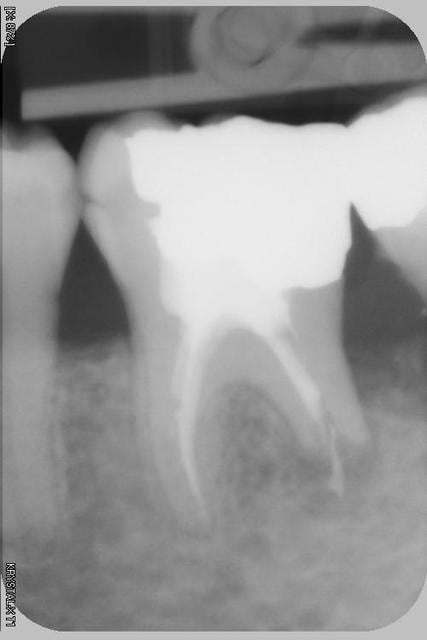

Maintenant que faire avec la 36 qui est pour le moment asymptomatique...reprise ou pas reprise de traitement? Si reprise, quelle(s) solution(s) pour la racine distale?

L'endo date d'avant 2003 seul moment ou je l'ai vu, et il n'a vu personne entre temps.

Si on regarde bien la pano, beaucoup de dents ont des racines résorbées. Les premières molaires sont celles qui semblent avoir le plus souffert. Peut-être à cause d'un traitement ortho.

La question qu'on peut se poser c'est si les rhizalyses sont actives ou pas. Si la cause est ortho et qu'aucun appareil n'est en place, est-il possible que les racines se résorbent encore davantage ?

La 37 n'est plus vivante...ou plutot pas de reponse au froid.